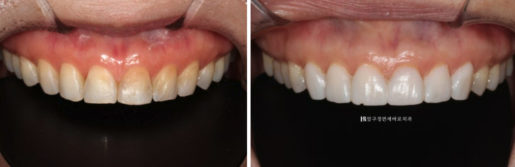

Let’s compare the photos from the initial visit / after 4 months of orthodontic treatment / after Gelami placement.

24.04~24.08

The worn and chipped edges of the teeth have been beautifully covered.

The uneven resin stains have also been concealed.

24.04-24.08

The last photo is after Gelami placement.

Even after placement, they are made so thin that there is little difference from the original teeth.

This photo gives an idea of Gelami’s thickness.